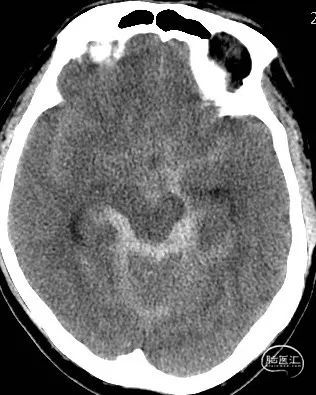

影像检查:CT提示广泛蛛网膜下腔出血(环池、四叠体池、桥前池、桥小脑角、三脑室),Fisher分级2级。CTA提示左侧大脑后动脉P2段动脉瘤,大小约2.3mm*1.3mm,颈宽约2.3mm。

术前影像

术前CT

影像检查:CT提示广泛蛛网膜下腔出血(环池、鞍上池、桥前池、侧裂池、侧脑室),Fisher分级3级。CTA提示右侧颈内动脉交通段动脉瘤。